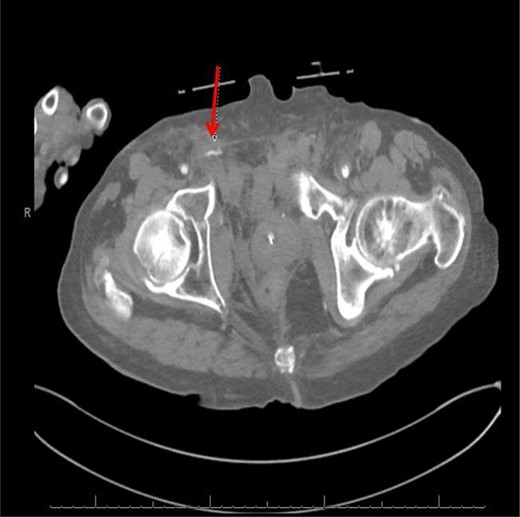

Computed tomography (CT) (axial view) of the abdomen and pelvis demonstrating blush of contrast from distal branch of the right internal iliac artery.

CT abdomen/pelvis with contrast was performed and a blush of contrast was noted posterior to the right pubic bone. Prior to taking patient for exploratory surgery, he was transferred to the interventional radiology suite where a pelvic angiogram was performed revealing an abnormal blush localized to the distal branches of the right iliolumbar artery (Fig. 2). Delayed phase of the angiogram demonstrated early venous filling consistent with a traumatic arteriovenous fistula which was embolized with 300–500 µ of embospheres and three 3 × 2 microcoils (Figs 3 and 4).